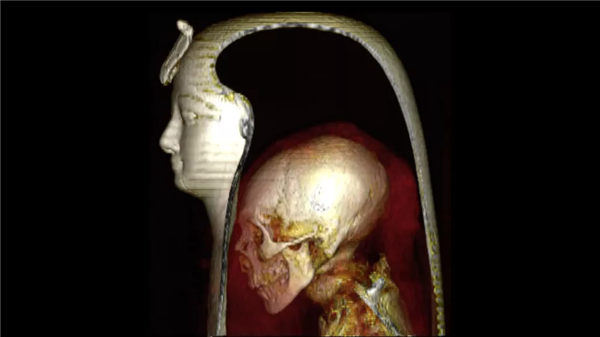

据外媒报道,近日,开罗大学医学院的研究人员通过CT三维重建,恢复了距今有大约有3500年历史的古埃及法老,阿蒙霍特普一世的生前面目。

为此,研究人员决定对阿蒙霍特普一世进行CT三维重建,这将有助于了解他最初怎么被制作成木乃伊的,以及死后被盗墓贼破坏后,后人又是如何修复他的。

结果发现,阿蒙霍特普一世的身高大约为168厘米,牙齿很好,他还接受过割礼。其相貌与他的父亲十分相似,下巴和鼻子都很窄小,头发卷曲,上牙略微突出。此外,研究人员还发现了30个护身符和一条十分独特的金腰带。

研究人员表示,CT图像同时揭示了阿蒙霍特普一世木乃伊的损伤程度,其颈部有骨折并被斩首,前腹壁缺失了一大块,并且四肢也与身体脱离。

遭到了严重破坏后,其后人将他脱离的肢体放回原位,并用树脂将这些肢体与身体固定在一起,并用新绷带重新对其进行了包扎。